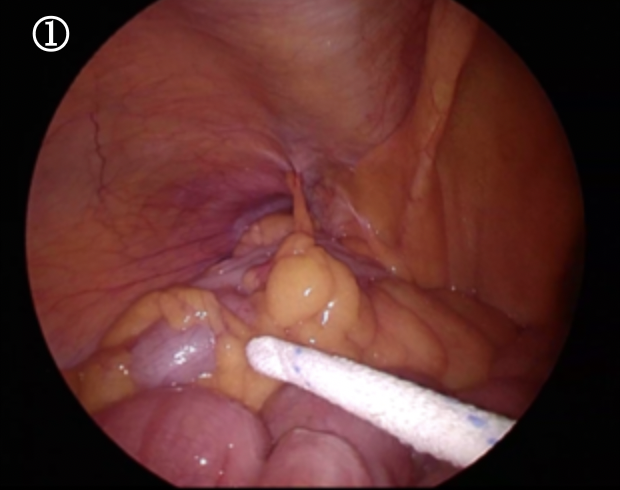

ソケイヘルニアをおなかの内側から見た写真です。ソケイ部に開いた大きな穴におなかの中の脂肪や腸が入り込んでいます。

まずはこれを引き出すことから始まります。これを引き出すと・・・・・